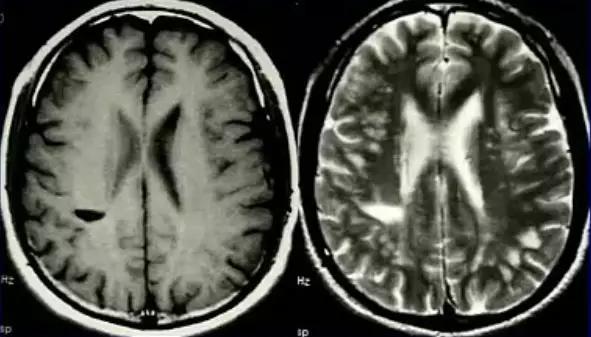

多位于侧脑室旁白质、半卵圆中心、也可位于脑干、颅神经等处,灰质核团受累少见,国人好发于脊髓、视神经

病灶呈卵圆形,沿侧脑室放射状分布,呈「垂直征」,长 T1、长 T2 信号,中心可囊变,活动期增强明显,静止期无增强,活动期 DWI 呈高信号